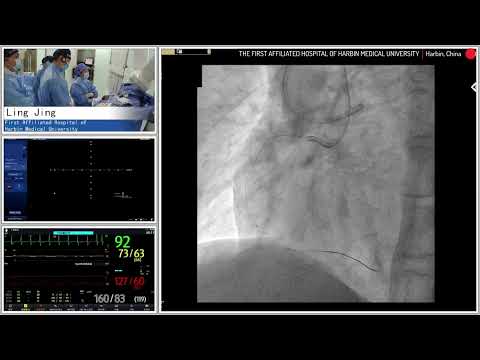

PCI of CTO RCA using Antegrade/Retrograde Approach - November 20, 2012 Webcast Video

PCI of RCA CTO using Antegrade or Retrograde Approach - July 17, 2018

Recanalization of a complex RCA CTO using Antegrade/Retrograde Approach

Recanalization of a complex RCA CTO using Antegrade Retrograde Approach - Oct 2019

Staged PCI of RCA CTO using Antegrade/Retrograde Approach - November 2022

PCI of mid RCA CTO via Antegrade/Retrograde Approach - December 2022